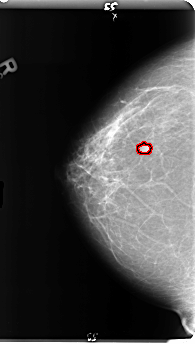

B_3146_1.RIGHT_CC

RIGHT_CC LINES 4816 PIXELS_PER_LINE 2728 BITS_PER_PIXEL 12 RESOLUTION 50 OVERLAY

FILE: B_3146_1.RIGHT_CC.OVERLAY

TOTAL_ABNORMALITIES 1

ABNORMALITY 1

LESION_TYPE MASS SHAPE LOBULATED MARGINS CIRCUMSCRIBED

ASSESSMENT 4

SUBTLETY 4

PATHOLOGY BENIGN

TOTAL_OUTLINES 1

BOUNDARY